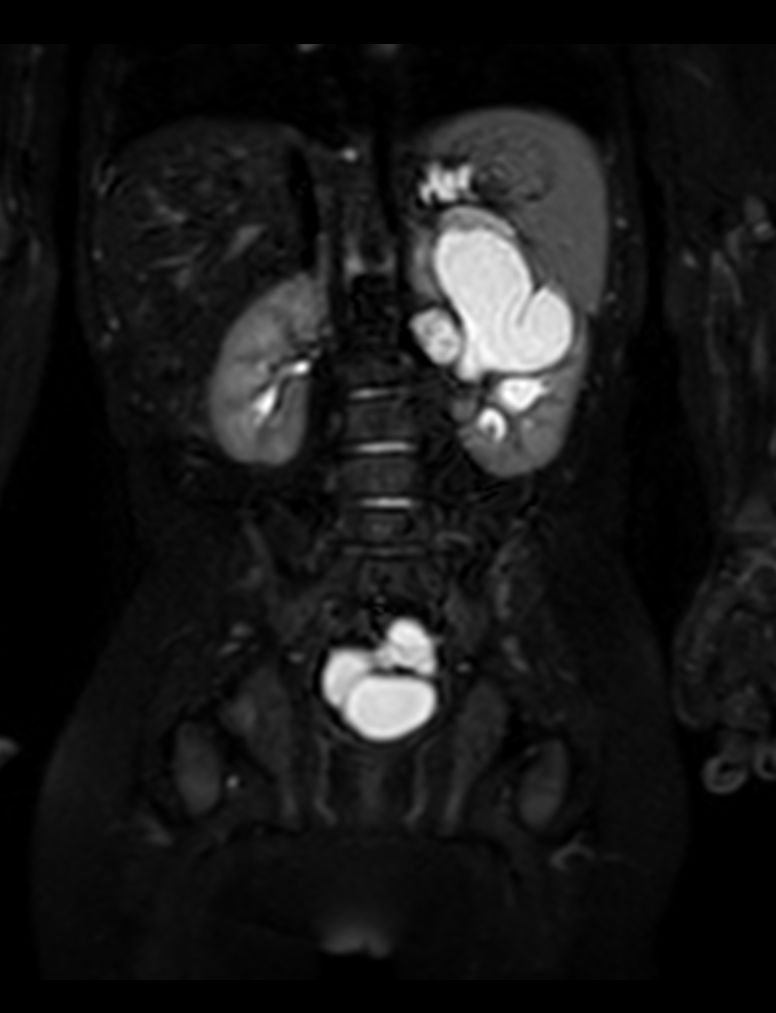

Coronal 3D VIEW T2w SPIR